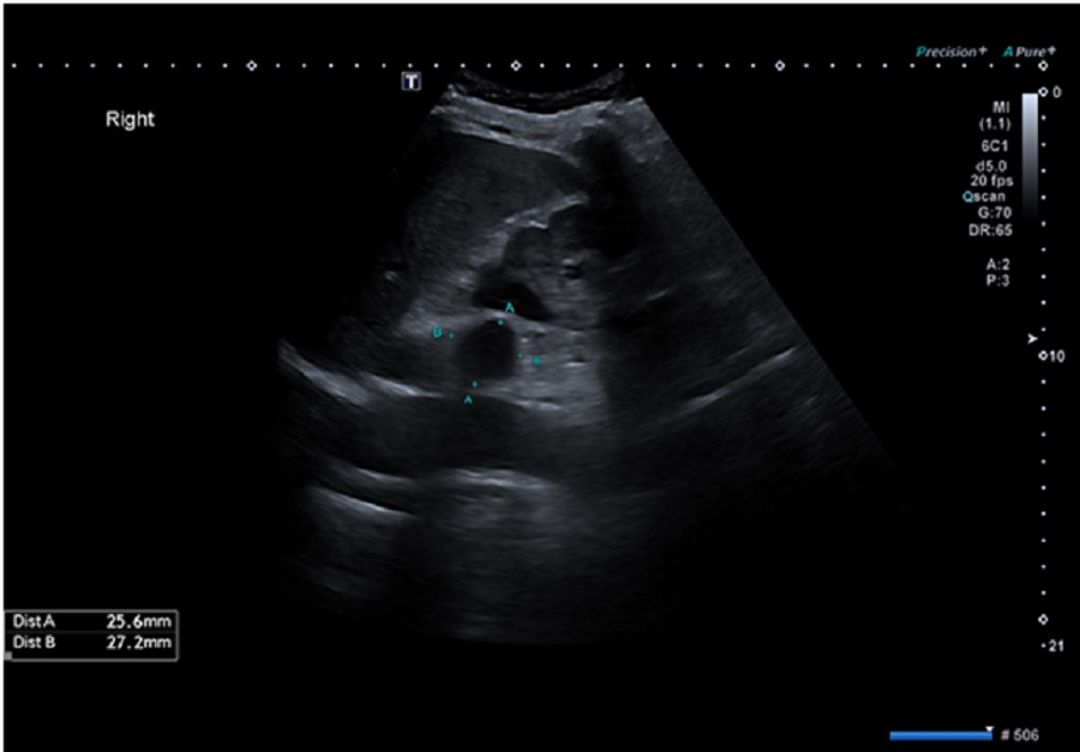

A 72-year-old male with diabetes mellitus and hypothyroidism, both well-managed, was referred after an incidental ultrasound finding of a 2.7 x 2.5 cm hypoechoic right adrenal nodule. He had no symptoms such as hypertension or Cushingoid features.

Figure 1 Figure 1: 2.5X2.7 cm hypoechoeic lesion in the right adrenal reported suspicious of adrenal adenoma